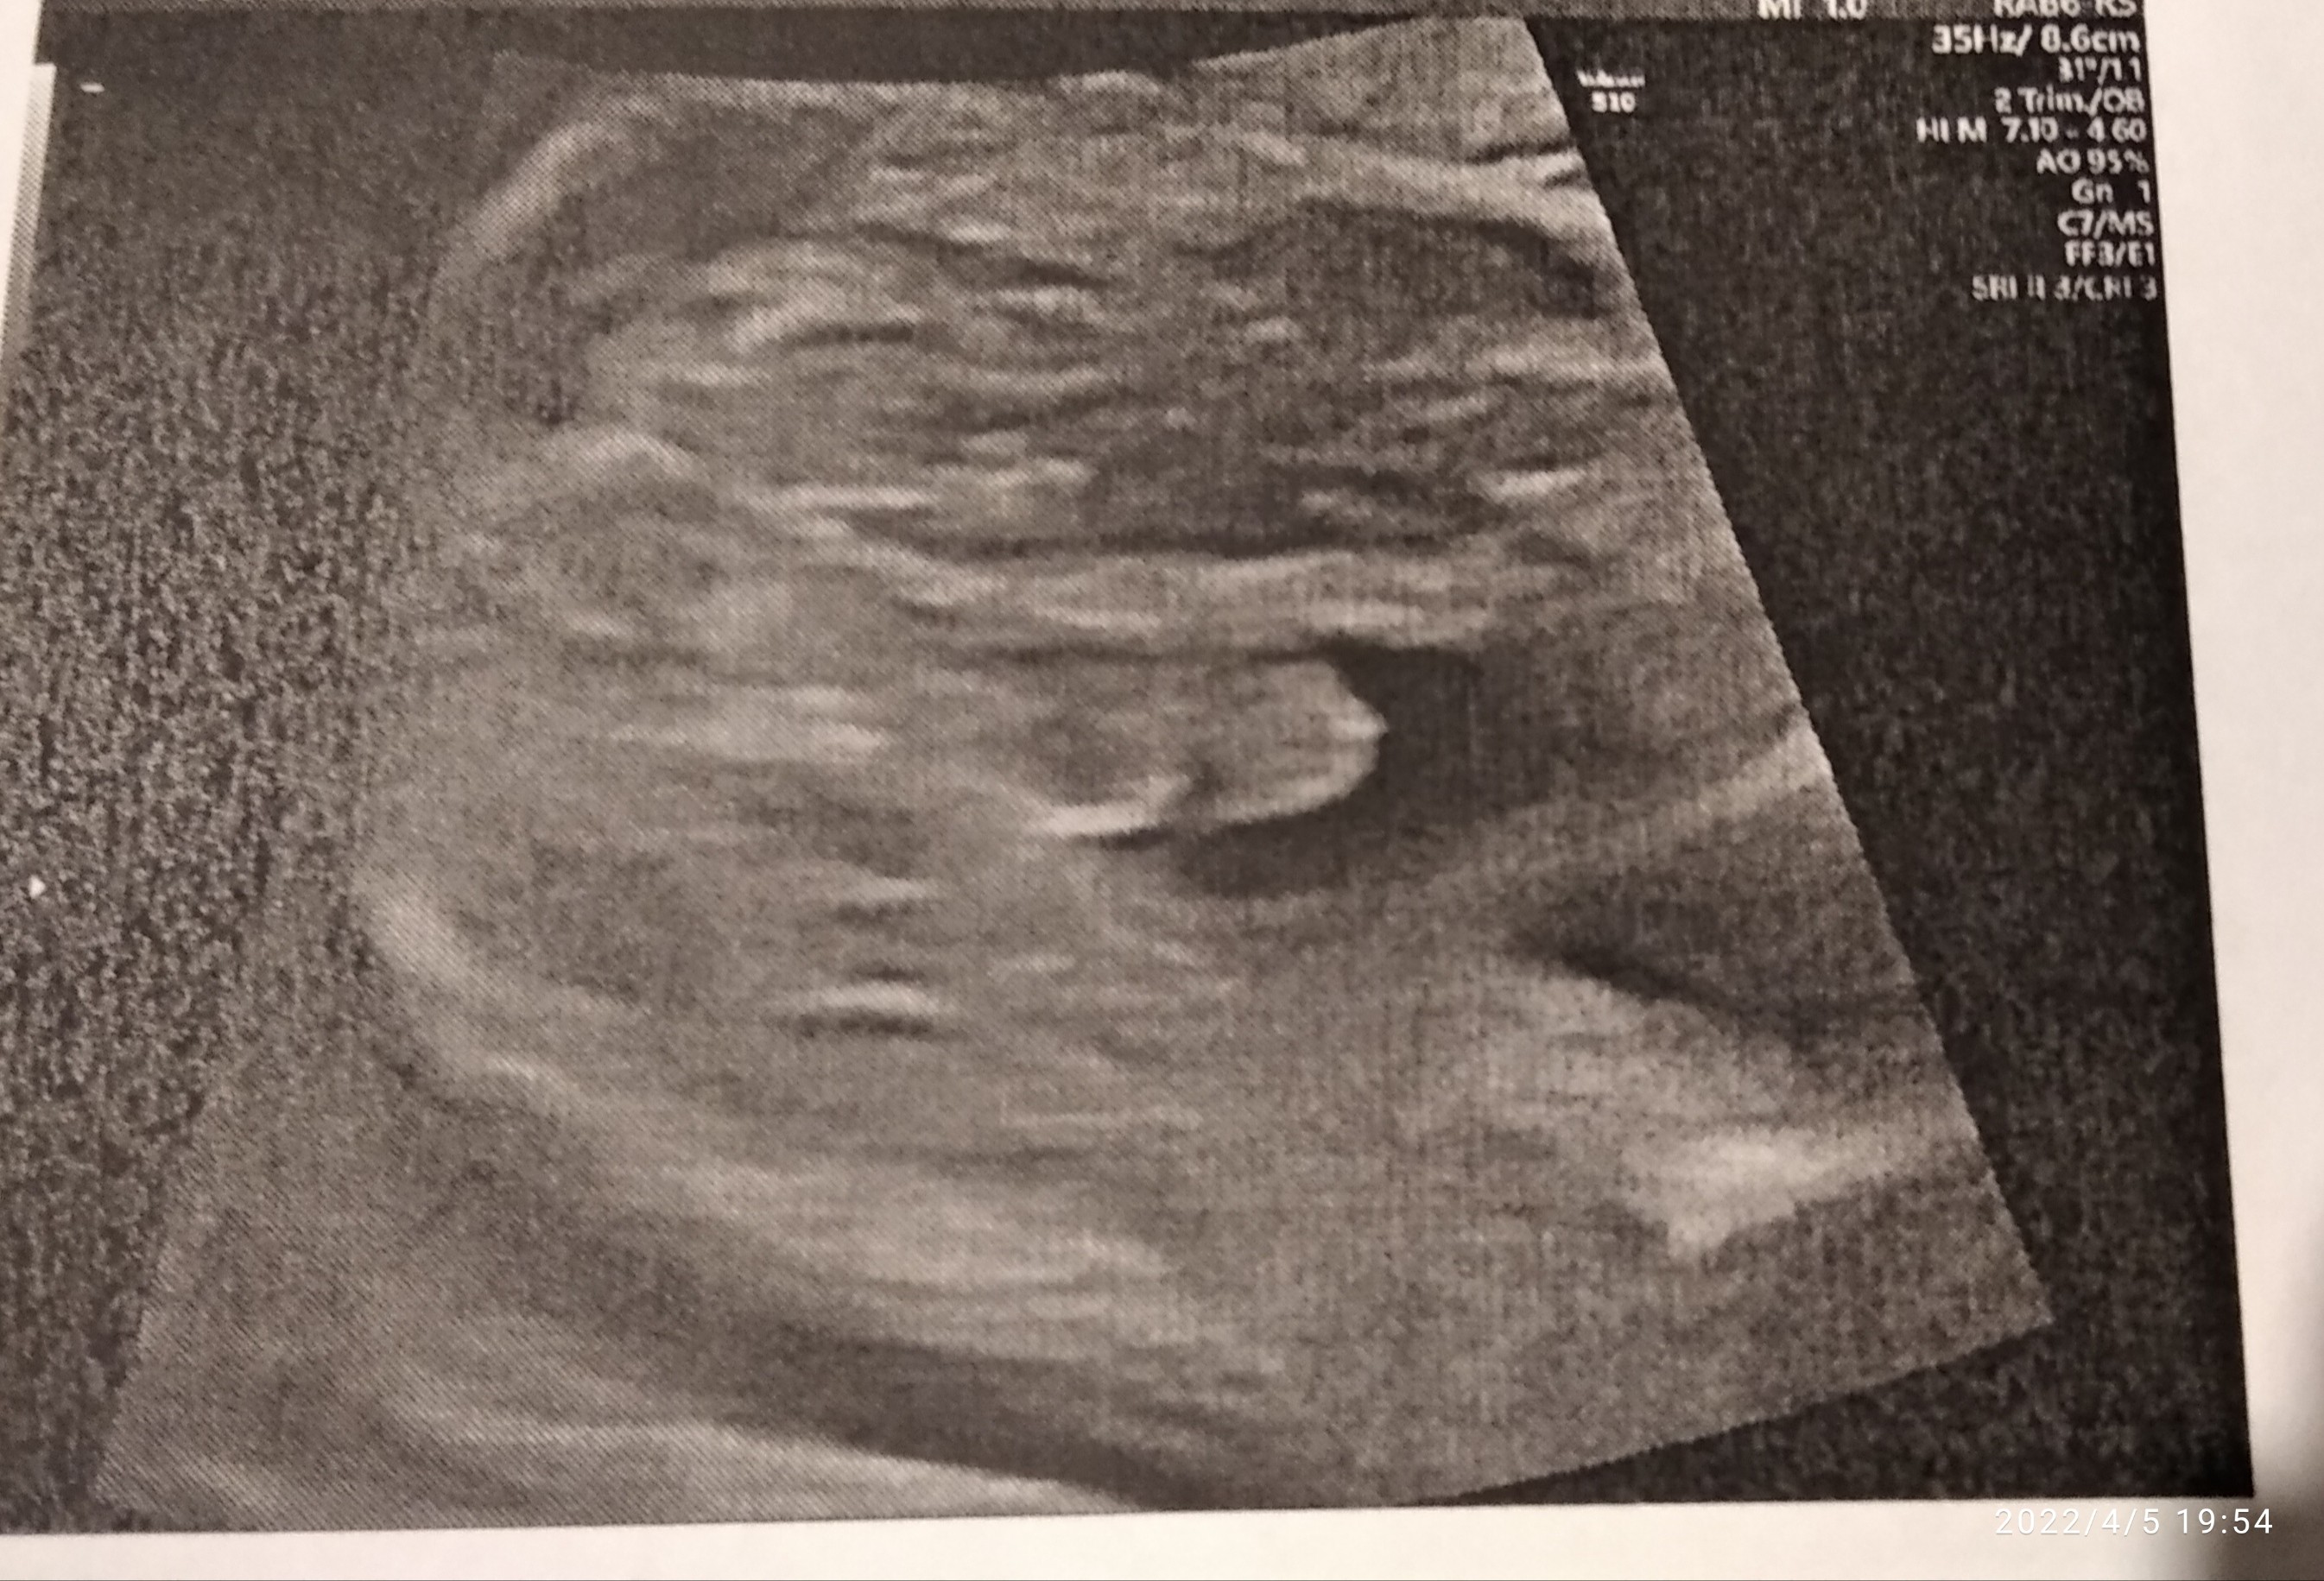

ja za to mimo tego że tutaj na moim zdjęciu niby nie widać pisiorka to i tak w 100% będę pewna kto jest po prenatalnych w 30tcTakteraz już nie ma żadnych wątpliwości

![]()

To trzymam kciuki żeby było po Twojej myślija za to mimo tego że tutaj na moim zdjęciu niby nie widać pisiorka to i tak w 100% będę pewna kto jest po prenatalnych w 30tc![]()